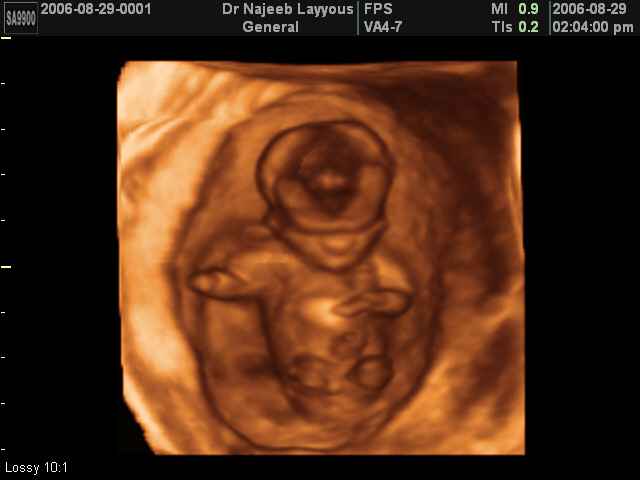

- First Trimester Ultrasound Photos

3D First Trimester Ultrasound Scan Photos ( Early Pregnancy Ultrasound Photos ) | Dr N Layyous